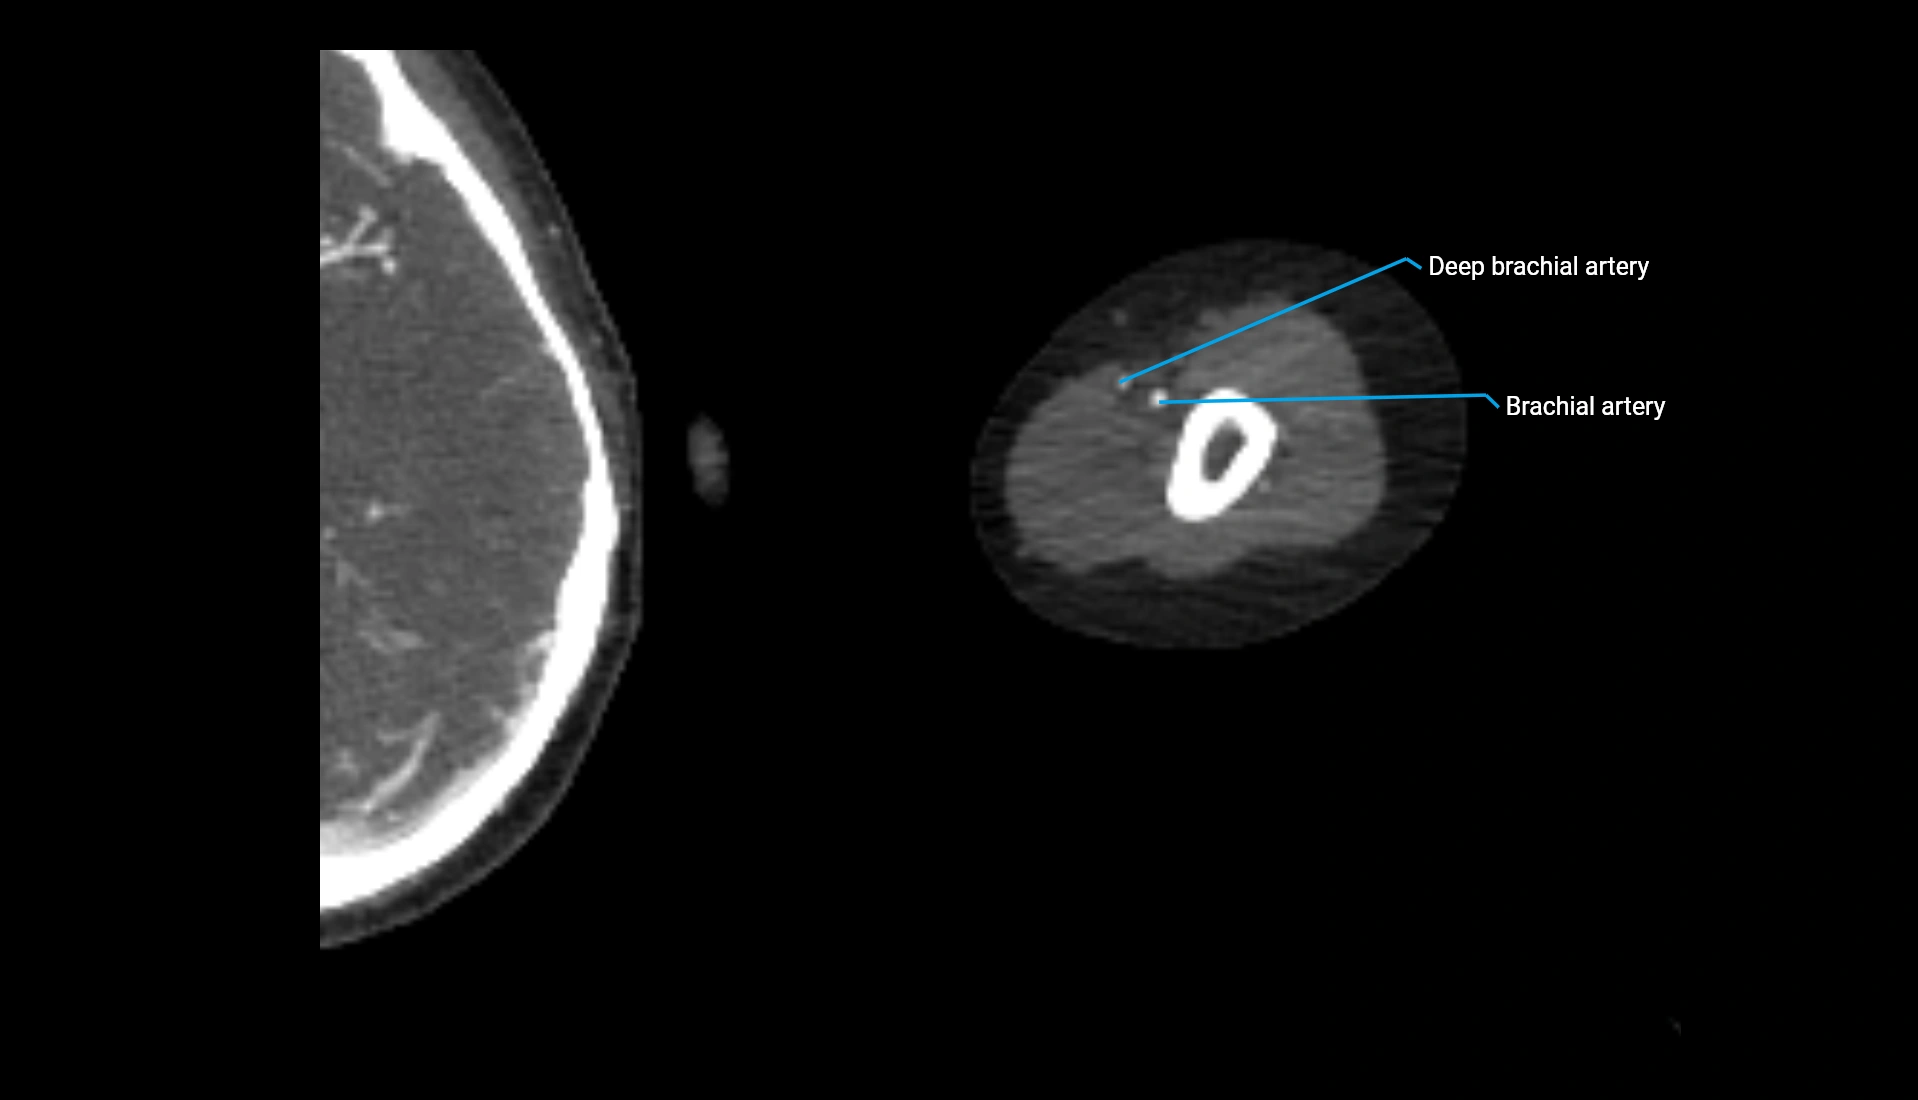

CT Appearance

Non-Contrast CT:

• Cortex: High-density, sharply defined

• Subchondral bone: Dense cancellous matrix

• Articular surface: Smooth concave contour articulating with the capitellum

• Excellent for evaluating bone integrity, alignment, and subtle fractures